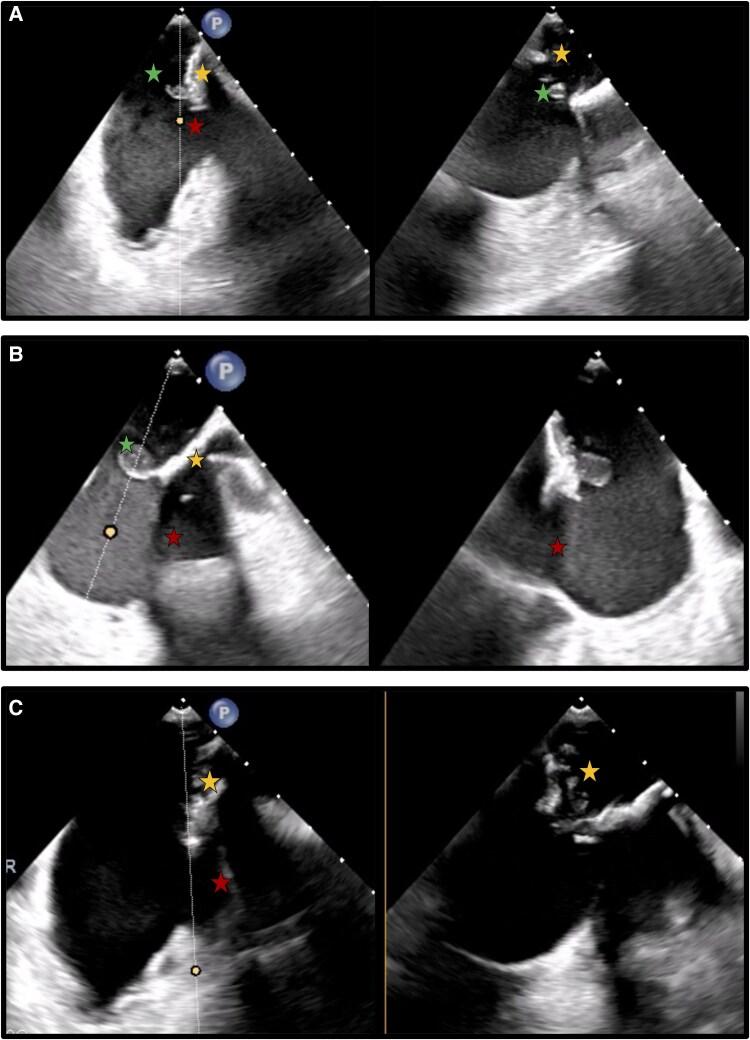

We describe the case of a 43-year-old Caucasian male with recurrent cardioembolic strokes due to a calcified, broken, and thrombosed baffle with floaty, anticoagulant-resistant thrombi adhered to the side of the pulmonary venous return of Mustard patch. Surgery was the only curative option due to thrombi recurrence under different regimes of anticoagulation.

A case of recurrent cardioembolic strokes long after Mustard surgery due to thrombi on a heavily calcified pericardial patch is presented. A fracture in the patch led to the exposure of thrombogenic material, which had accumulated around the pacemaker (PM) leads on the systemic venous side of the baffle. This exposure allowed thrombotic material to reach the pulmonary venous side, ultimately entering the subaortic right ventricle and the systemic circulation. In the Mustard procedure, the material used for the baffle construction is prone to degeneration and calcification over time. We hypothesize that chronic mechanical stress from the PM leads might have contributed to the gradual erosion and fracture and consequently thrombosis of the heavily calcified patch, leading to recurrent strokes. Surgery became necessary as aggressive anticoagulation failed to prevent thrombus recurrence.

本文报告了一例Mustard手术后很久因严重钙化的心包补片上的血栓导致反复心源性栓塞性卒中的病例。补片骨折导致血栓形成物质暴露,这些物质积聚在挡板体静脉侧的起搏器(PM)导线周围。这种暴露使血栓形成物质到达肺静脉侧,最终进入主动脉下右心室和体循环。在Mustard手术中,用于构建挡板的材料随着时间的推移容易发生变性和钙化。我们推测,PM导线产生的慢性机械应力可能导致了严重钙化补片的逐渐侵蚀、骨折,进而导致血栓形成,引发反复卒中。由于积极抗凝未能预防血栓复发,手术成为必要手段。